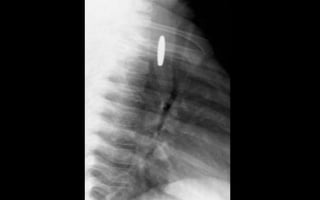

MARCADOR

1

2

3